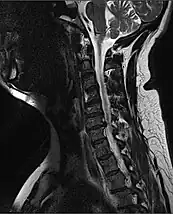

![]() | |

| MRI of fractured and dislocated neck vertebra that is compressing the spinal cord | |

A radiographic evaluation using an X-ray, CT scan, or MRI can determine if there is damage to the spinal column and where it is located.[15] X-rays are commonly available[60] and can detect instability or misalignment of the spinal column, but do not give very detailed images and can miss injuries to the spinal cord or displacement of ligaments or disks that do not have accompanying spinal column damage.[15] Thus when X-ray findings are normal but SCI is still suspected due to pain or SCI symptoms, CT or MRI scans are used.[60] CT gives greater detail than X-rays, but exposes the patient to more radiation,[62] and it still does not give images of the spinal cord or ligaments; MRI shows body structures in the greatest detail.[15] Thus it is the standard for anyone who has neurological deficits found in SCI or is thought to have an unstable spinal column injury.[63]